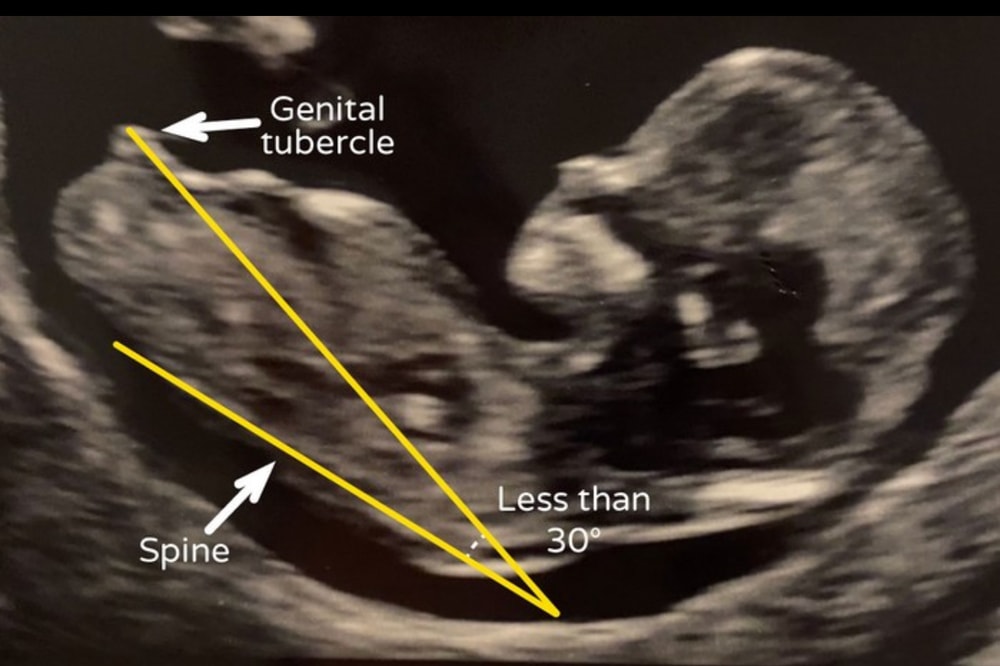

Как работает определение пола в 11-13 недель УЗИст смотрит угол наклона генитального бугорка относительно позвоночника: Если бугорок направлен вверх под углом > 30° - чаще всего мальчик. Если параллельно позвоночнику или вниз - чаще всего девочка. Изображение